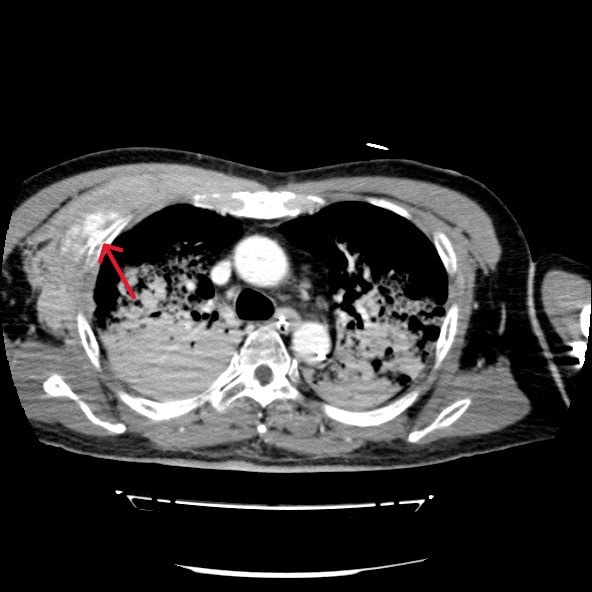

心筋梗塞によって心室細動をきたし心肺停止状態で当院に救急搬送された症例。救命活動が行われ心肺蘇生することができた。その後の経皮的冠動脈インターベンション(Percutaneous Coronary Intervention:PCI)の施行中に経皮的心肺補助法(Percutaneous Cardiopulmonary Support:PCPS)からの脱血不良あり循環血漿量減少が著明に進行していたため、原因精査目的に造影CTを撮影したところ、右第3肋骨周囲の前胸部に血管外漏出(extravasation)が認められた。

胸骨圧迫による動脈損傷が考えられたため、当院放射線科医師により緊急アンギオが施行された。右最上胸動脈および胸肩峰動脈からの出血が確認され、動脈塞栓術(TAE)にて止血することができた。

胸骨圧迫は心肺蘇生において不可欠な救命処置であるが、強い外力により外傷性合併症のリスクが存在する。代表的な合併症としては肋骨骨折や胸骨骨折の頻度が最も高く報告されており、血胸や胸壁血腫などの出血性合併症は報告により約10%程度とされている。ただし、出血源については明確ではなく、動脈損傷に関する症例報告は非常に稀である。特に内胸動脈や肋間動脈、最上胸動脈などの小血管損傷は画像検査が実施されなければ見逃される可能性が高く、臨床的にも認識されにくい。

本症例は、胸骨圧迫後に右最上胸動脈および胸肩峰動脈からの出血を認めた合併症例である。これまでの文献においても、胸骨圧迫後にこれらの動脈からの出血が明確に確認された症例はほとんど存在せず、本症例はその点で非常に特異性が高い。

本症例においては造影CTが循環不全の原因特定、胸骨圧迫による血管損傷の可視化、出血量評価、他臓器損傷のスクリーニングおよび治療方針の決定に有用であった。本症例のような稀な合併症を見逃さないためにも、胸骨圧迫後の症例では、一般的な骨折だけでなく、稀な血管損傷の可能性も念頭に置き、早期に造影CTによる精査を積極的に行うことが重要である。